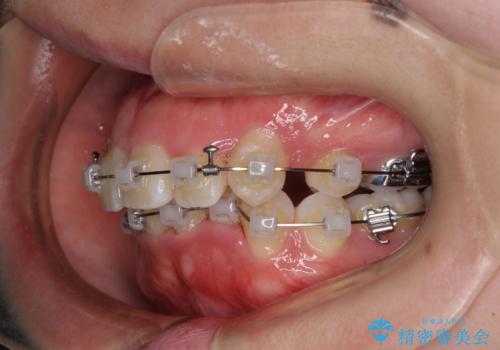

- 矯正装置

- クリアブラケット

- 上下の八重歯やデコボコを気にして来院された患者様です。

上下ともに八重歯が顕著であったので、上下左右第一小臼歯4本を抜歯し、補助装置を使用して速やかに改善しながら、ワイヤー装置にて矯正治療を行うこととしました。

気になっていた八重歯は装置装着から3か月ほどで解消されました。

2年以内を目標として治療を開始しましたが、1年半ほどで終えることができました。